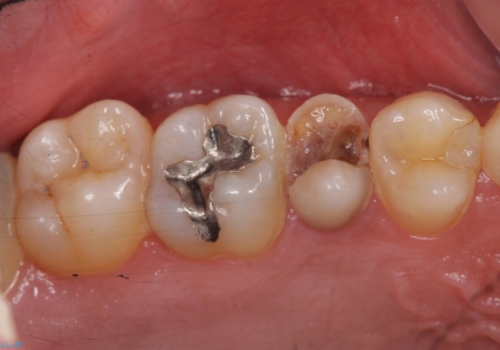

歯の健康な部分を矯正治療で引っ張り出してから、虫歯治療を行なっています。

治療途中